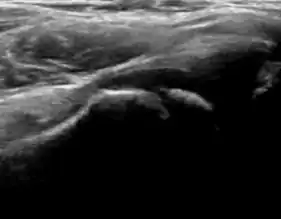

Ultrasound

Ultrasound is the first-choice technique for diagnosis of newborns hip dysplasia. In experienced hands with appropriate technology, ultrasound can also be useful during the first year of life. Some European healthcare systems encourage universal ultrasound screening in neonates between the sixth and eighth weeks. Although it shows higher initial costs caused, it leads to significant reduction in the total number and overall costs of dysplastic hips undergoing operative and nonoperative treatment.[1]

Ultrasound allows categorizing pediatric hips, according to Graf’s criteria, in four main types: normal, immature, and dysplastic (subluxed and dislocated). This classification is based on measurements of the acetabular inclination angle (alpha), cartilage roof angle (beta), and infant age. The femoral head coverage can also be determined by dividing the length of the femoral head covered by the acetabular fossa and the diameter of the femoral head. Its lower normal limits are 47% for boys and 44% for girls (Figure 11).[1]

Useful ultrasound measures in neonatal hip sonography, alpha and beta angles.[1] -

Measurement of femoral head coverage.[1]

During childhood, ultrasound is a quick method to assess hip pain and quite often may be used to avoid use of irradiating techniques, such as radiography or CT. Ultrasound allows evaluation of joint effusion, synovial thickening and neovascularity, the bone/cartilage contour, and the femoral head-neck alignment. Although sonography is extremely sensitive in detecting increased synovial fluid, it is nonspecific and cannot be used with accuracy to determine the type of fluid. Transient synovitis of the hip, despite being the most frequent cause of pain in children between 3 and 10 years, remains a diagnosis of exclusion. It usually shows anechoic fluid, but echogenic fluid can also be found. The effusion is considered pathologic when it is measured at >2 mm in thickness. The differential diagnosis is wide, including osteomyelitis, septic arthritis, primary or metastatic lesions, LCPD, and SCFE. Discrimination from septic arthritis is challenging, often requiring joint aspiration. In septic arthritis, US is able to demonstrate a hip joint effusion, synovial thickening, and cartilage damage, although the appearances are nonspecific.[1]